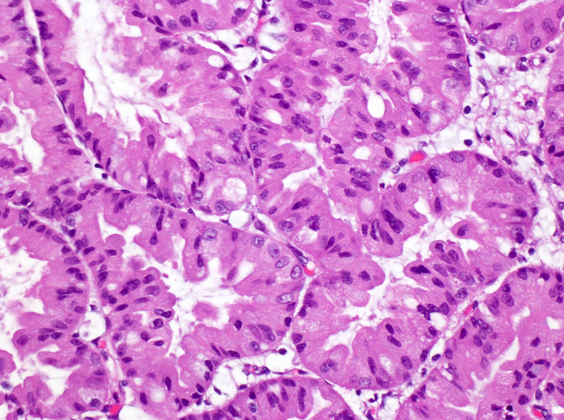

Intraductal oncocytic papillary n

Essential: a complex arborizing papillary neoplasm with oncocytic epithelial features; location within a cystically dilated duct; examine carefully for an associated invasive carcinoma (30%). (NB: essentially all have HGD)

IHC: Diffusely EMA (MUC1) and MUC6 (+). MUC2 and MUC5AC (+) in goblet cells. Consistently Hep Par-1 (+)

Lacks the molecular alterations seen in ductal adenocarcinoma and IPMN)

Below: The cells have distinctive oncocytic cytoplasm and nuclei with single, prominent nucleoli. Intracellular lumina are also seen.